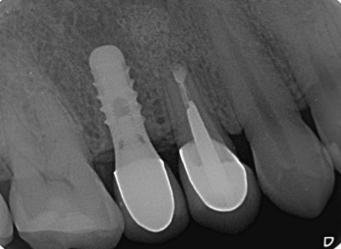

根尖切除術

治療後